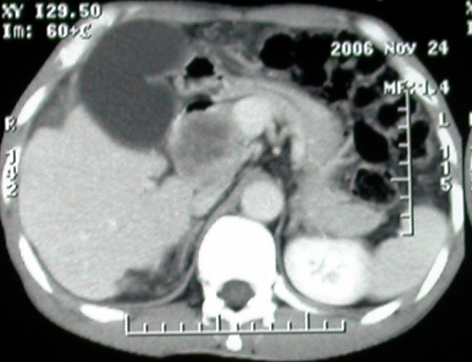

增强ct所见【动脉增强期】

增强ct所见